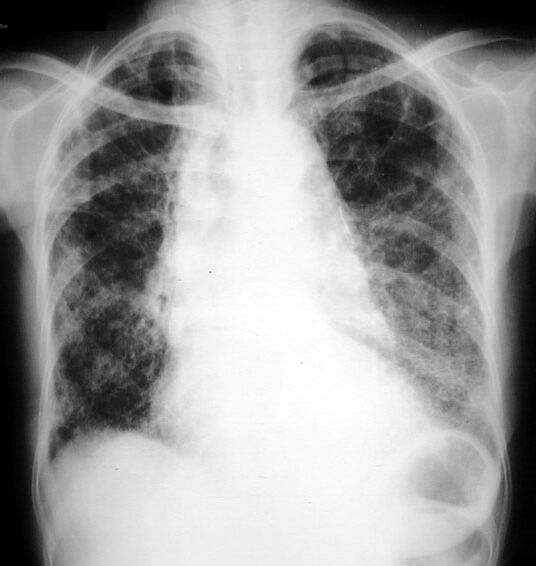

Lymphangitic Metastasis

Cancer Breast

Missing right breast Bilateral diffuse interstitial changes Uncoiling of aorta